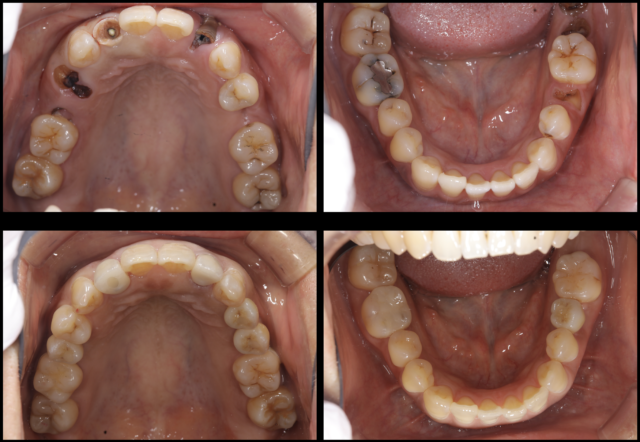

初診時口腔内

虫歯・歯周病の進行が著しく、審美障害を呈している

咬合面観 術前・術後比較

右上5番4番、左上2番5番、右下5番はインプラント補綴

右上2番はジルコニアクラウン補綴